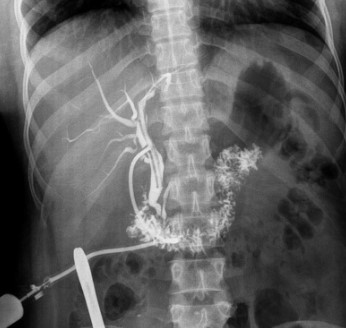

Percutaneous transhepatic cholangiography is an x-ray test that can help show whether there is a blockage in the liver or the bile ducts that drain it. Since the liver and its drainage system do not usually show up on X-rays, the doctor doing the X-ray needs to inject a special dye directly into the drainage system of the liver. This dye, visible on X-rays, should then spread out to fill the drainage system. If it does not, that means there is a blockage. This type of blockage might result from a gallstone or a cancer in the liver.

A separate needle is inserted between two ribs on your right side. The needle is advanced into your liver. A small amount of X-ray dye is injected, and some pictures are taken that are visible on a video screen. Your doctor adjusts the needle placement until it is clear that the dye is flowing quickly through the ducts (drainage tubes) inside your liver.

Then, more dye is injected through the plastic tube, and pictures are taken with the video camera as the dye spreads inside the liver. If there is no blockage, the dye drains out of the liver through the bile ducts and begins to show up on the x-ray in your small intestine. Once all the needed pictures have been taken, the plastic tube is pulled out, and a small bandage is placed over your side. The whole test usually takes less than an hour.